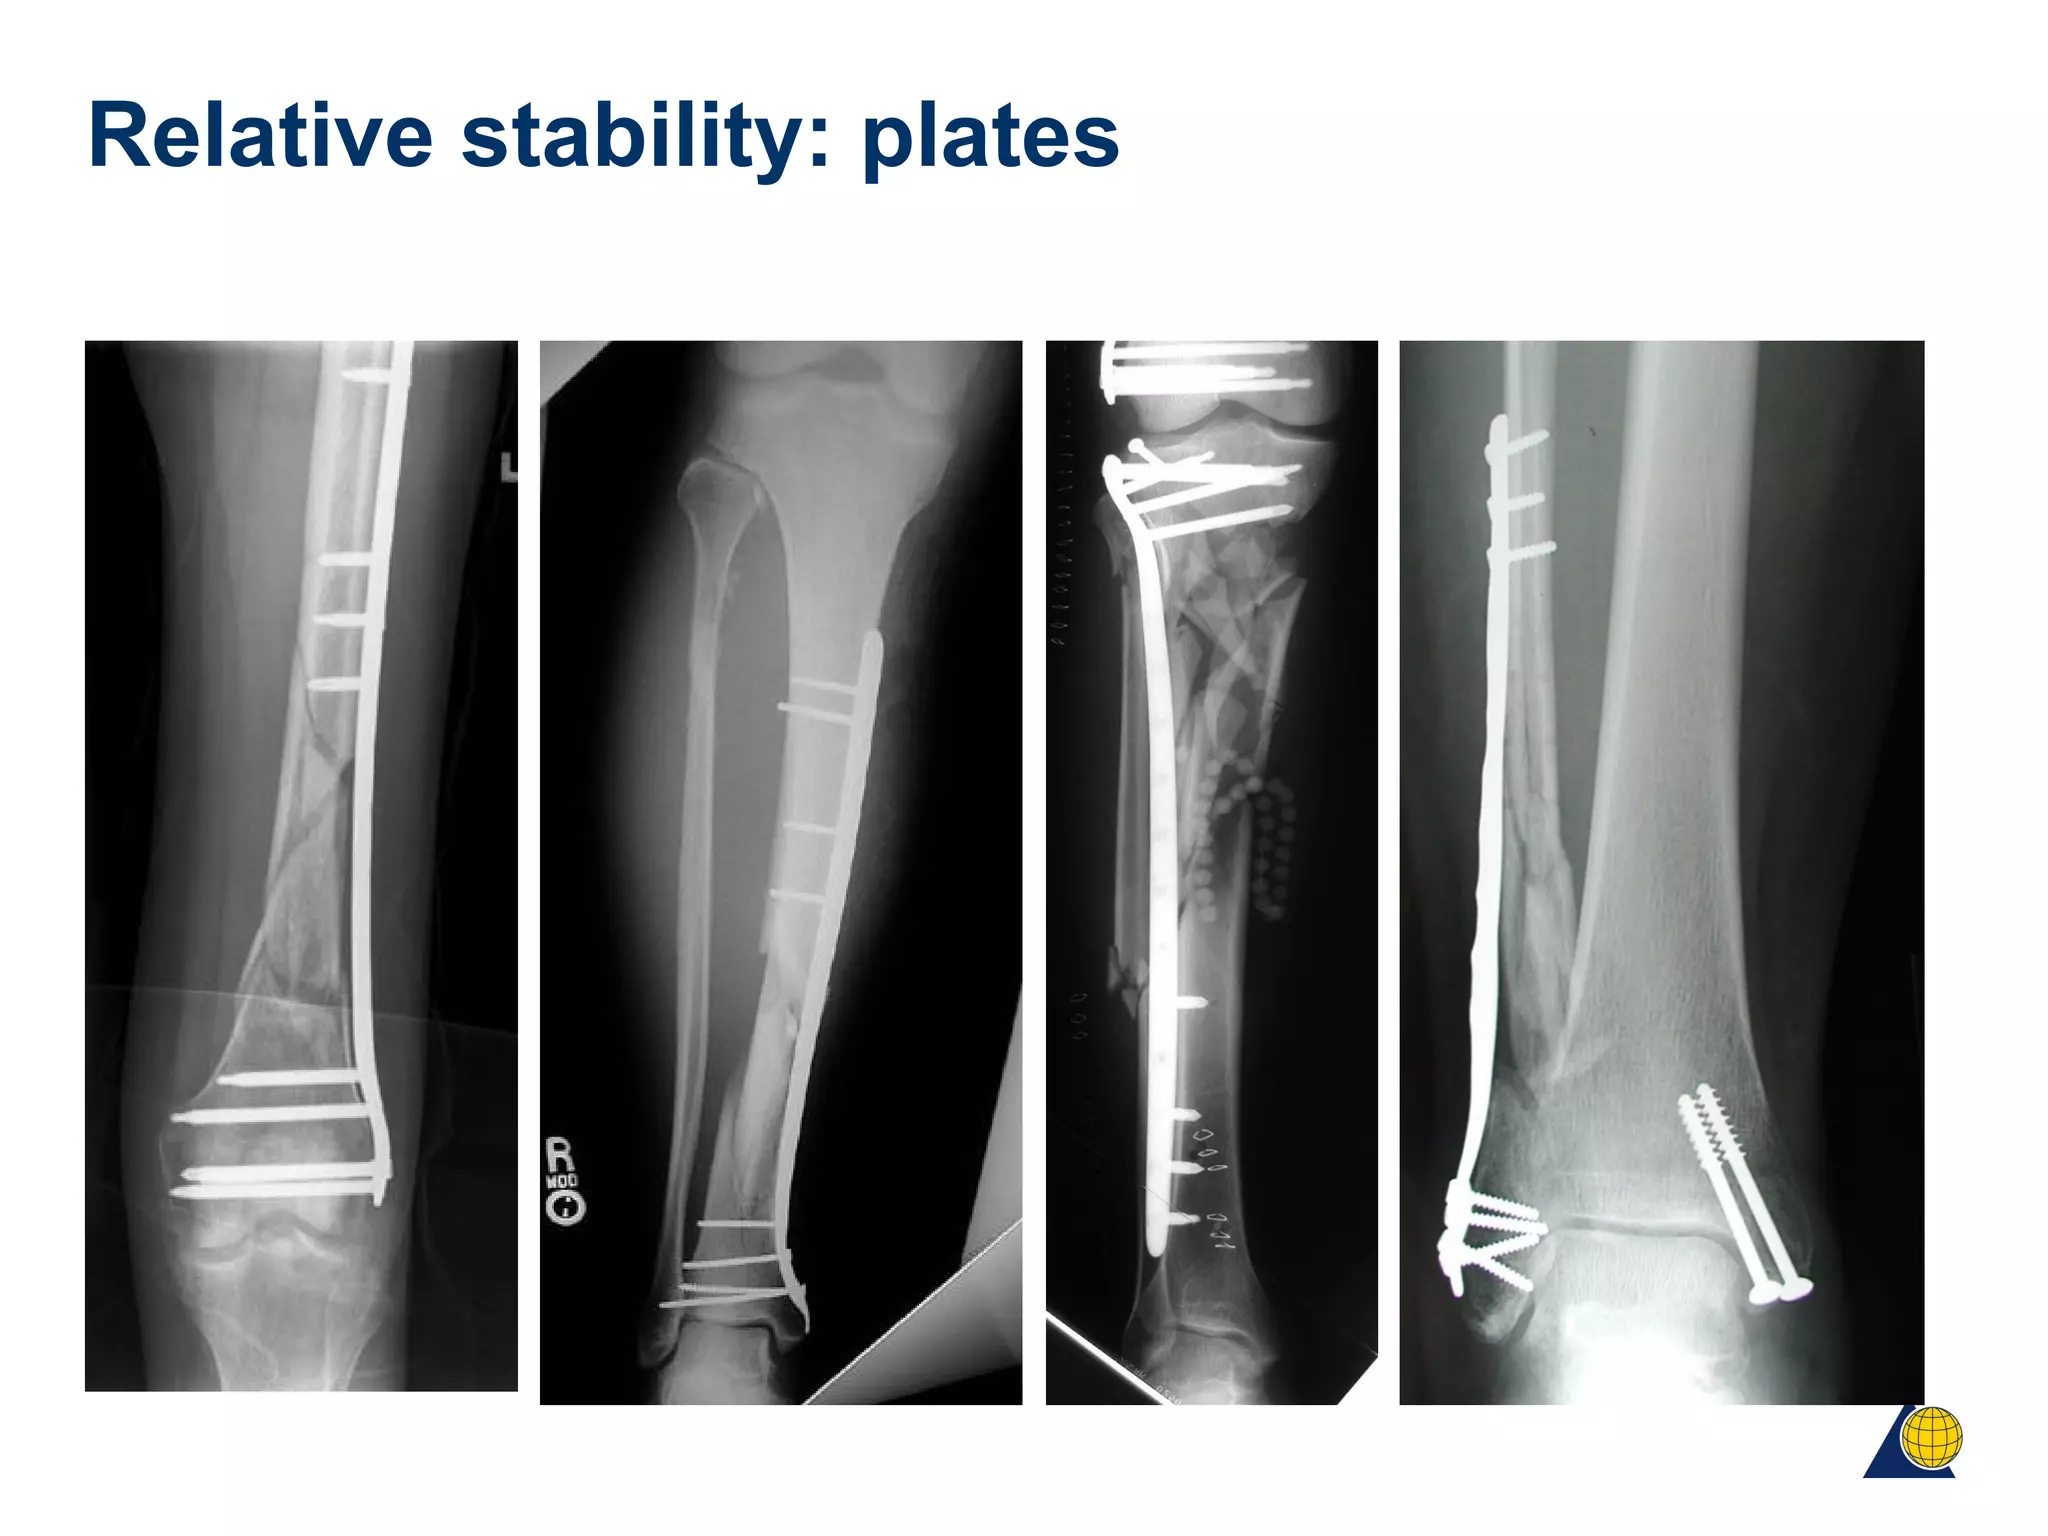

Relative stability: plates

• Extraperiosteal exposure of bone

• Indirect reduction to achieve anatomic alignment

• Implants that minimize bone necrosis

• Longer plates

• Judicious use of screws with balanced fixation

• Infrequent bone grafting